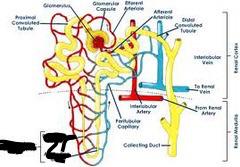

Afferent/efferent arteriole

Collecting duct

Distal (convoluted) tubule

Glomerular capsule (=Bowman's capsule)

Glomerulus (=glomerular capillaries)

Juxtaglomerular apparatus

Nephron

Peritubular capillaries

Proximal (convoluted) tubule